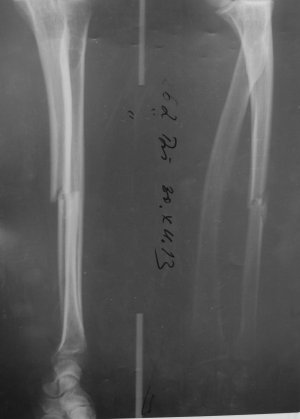

Добрый день. Мне 54г. 28.12.2013 во время неудачного ограбления (грабили меня) получил перелом правой руки, со смещением. Доктор говорит, что пока операцию с наложением пластины делать не стоит, может срастется нормально. Но я работаю за компьютером...и что то рука болит с опуханием периодически...и последний снимок мне абсалютно не нравиться...что то мне все грустнее и грустнее. Вопрос: может мне настоять на операции? Мне очень нужна полноценная правая рука.. Фотосесию флюорограм предоставлю. Помогите пожалуйста добрым совет